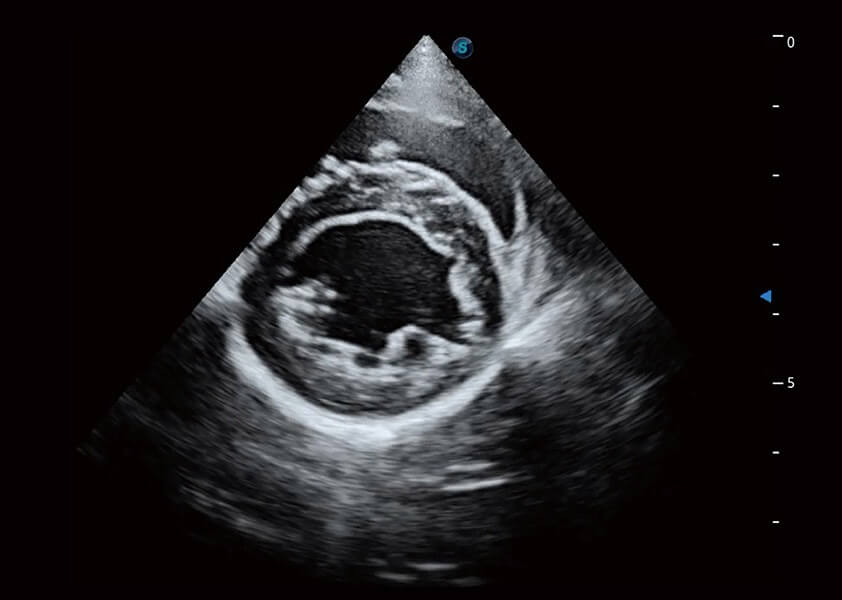

ProPet 60 作为一款高端台式动物超声设备,为动物医生的日常诊断提供了一系列贴合动物临床需求、解决临床实际问题的高级成像功能。凭借全系列高清探头,满足医生对腹部、心脏、生殖、浅表、肌骨等成像的所有需求,切实帮助您提升检查效率,提高诊断信心。

兽用彩色多普勒超声诊断系统

动物是人类最亲密的朋友和最值得信赖的伙伴。16877太阳集团也一直致力于探索动物专用的超声影像解决方案。 全新推出的ProPet系列,是16877太阳集团在动物超声影像智能化、专业化、精准化的一次跨越式革新。动物不能用言语来表述自己的不适,通过超声影像,ProPet系列搭建了动物医生与不同物种沟通的“桥梁”,为动物医生注入了“治愈之力”。